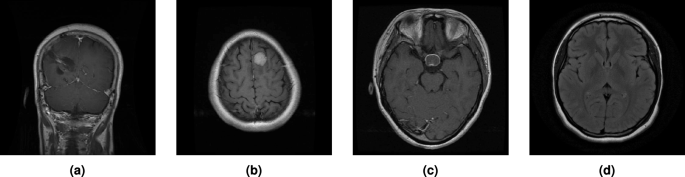

MRI images of four types of brain tumors. (a) Glioma, (b) Meningioma, (c) Pituitary, (d) No tumor.

The validation and test sets were only subjected to resizing and normalization, without any augmentation, to ensure a fair evaluation. Figure 5 shows example MRI images for each of the four tumor categories in the brain tumor MRI dataset.